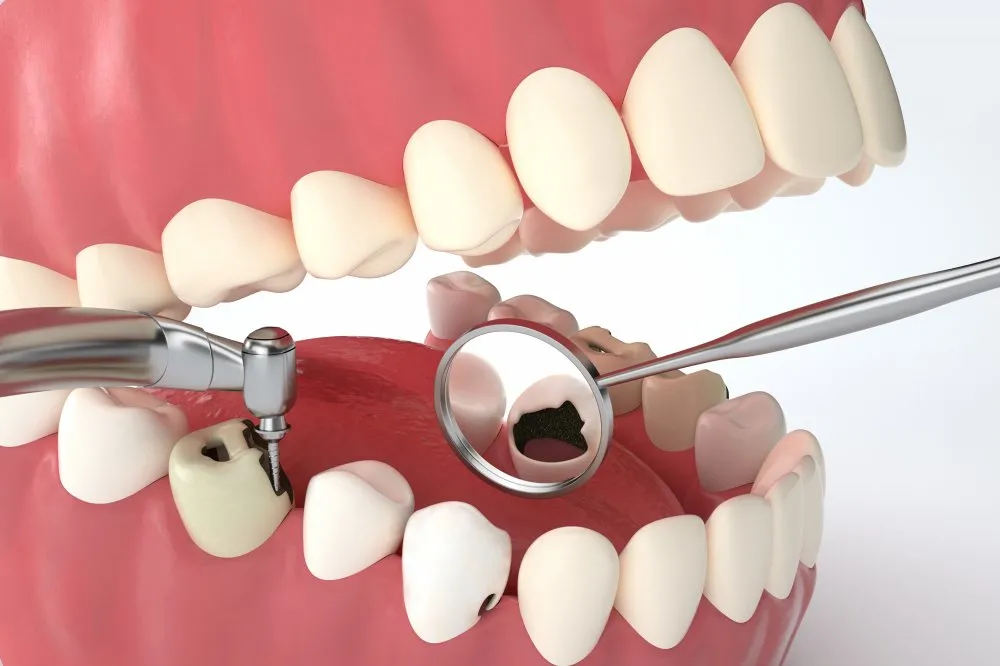

这张图就是给牙齿“填坑”的详细步骤

窝沟封闭

就是在牙齿上洗洗涂涂

不会痛的哟

孩子张嘴配合医生操作即可